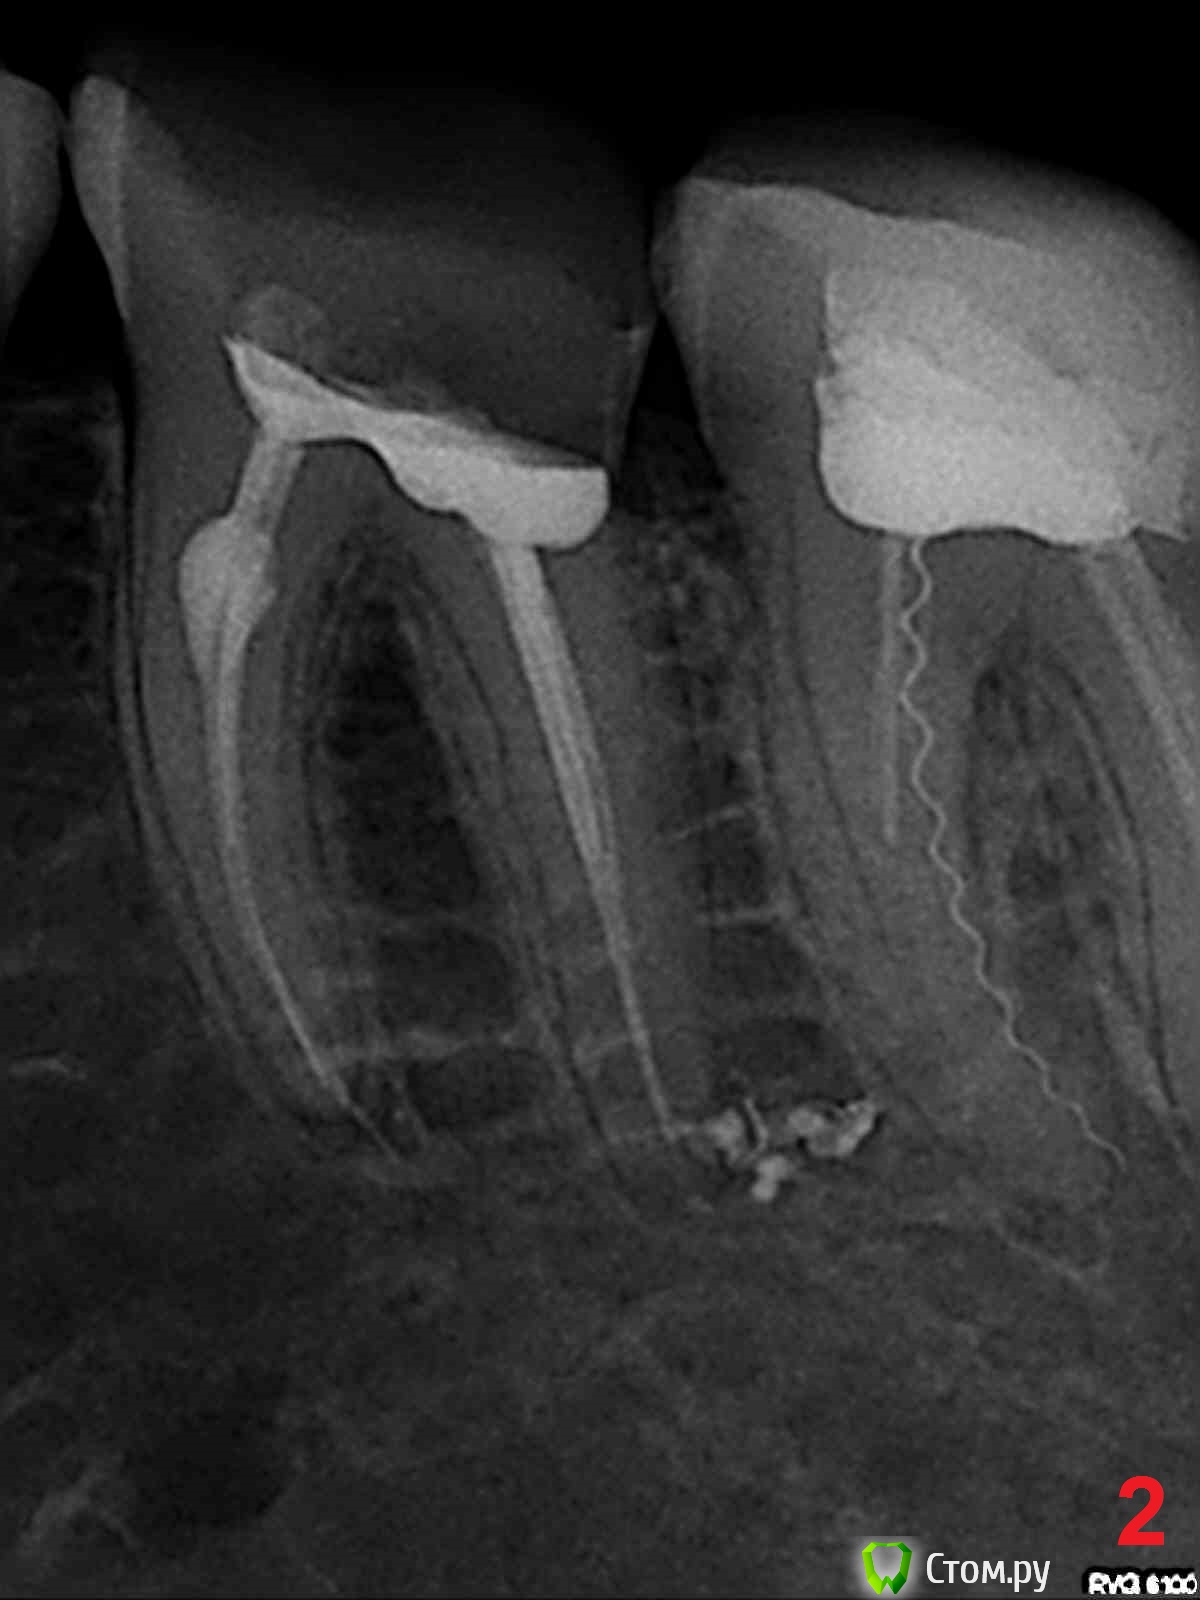

edw Опубликовано 16 июня, 2014 Поделиться Опубликовано 16 июня, 2014 Здравствуйте.Год назад в стоматологии прочистили каналы 36 (вроде) зуб, снимок 1. Месяцев через 7 после лечения появилась нарастающая все сильней боль, в итоге нажимать на зуб даже языком было очень больно. Пошел в эту же стоматологию, этот же врач переделал зуб по гарантии, снимок 2. Было больновато, как будто снова нервы не удалили до конца в прошлый раз. После перелечивания прошло уже месяца 2-3, зуб побаливает перидически, ноет, на горячее реагирует, например. Прошу знающих людей посмотреть снимки, сильно ли все плохо, и чем грозит? Хочу начать эпопею по возврату денег. 1 Ссылка на комментарий

Scrabble Опубликовано 16 июня, 2014 Поделиться Опубликовано 16 июня, 2014 И 37 перелечите-там сломан инструмент, и всё такое прочее. Ссылка на комментарий